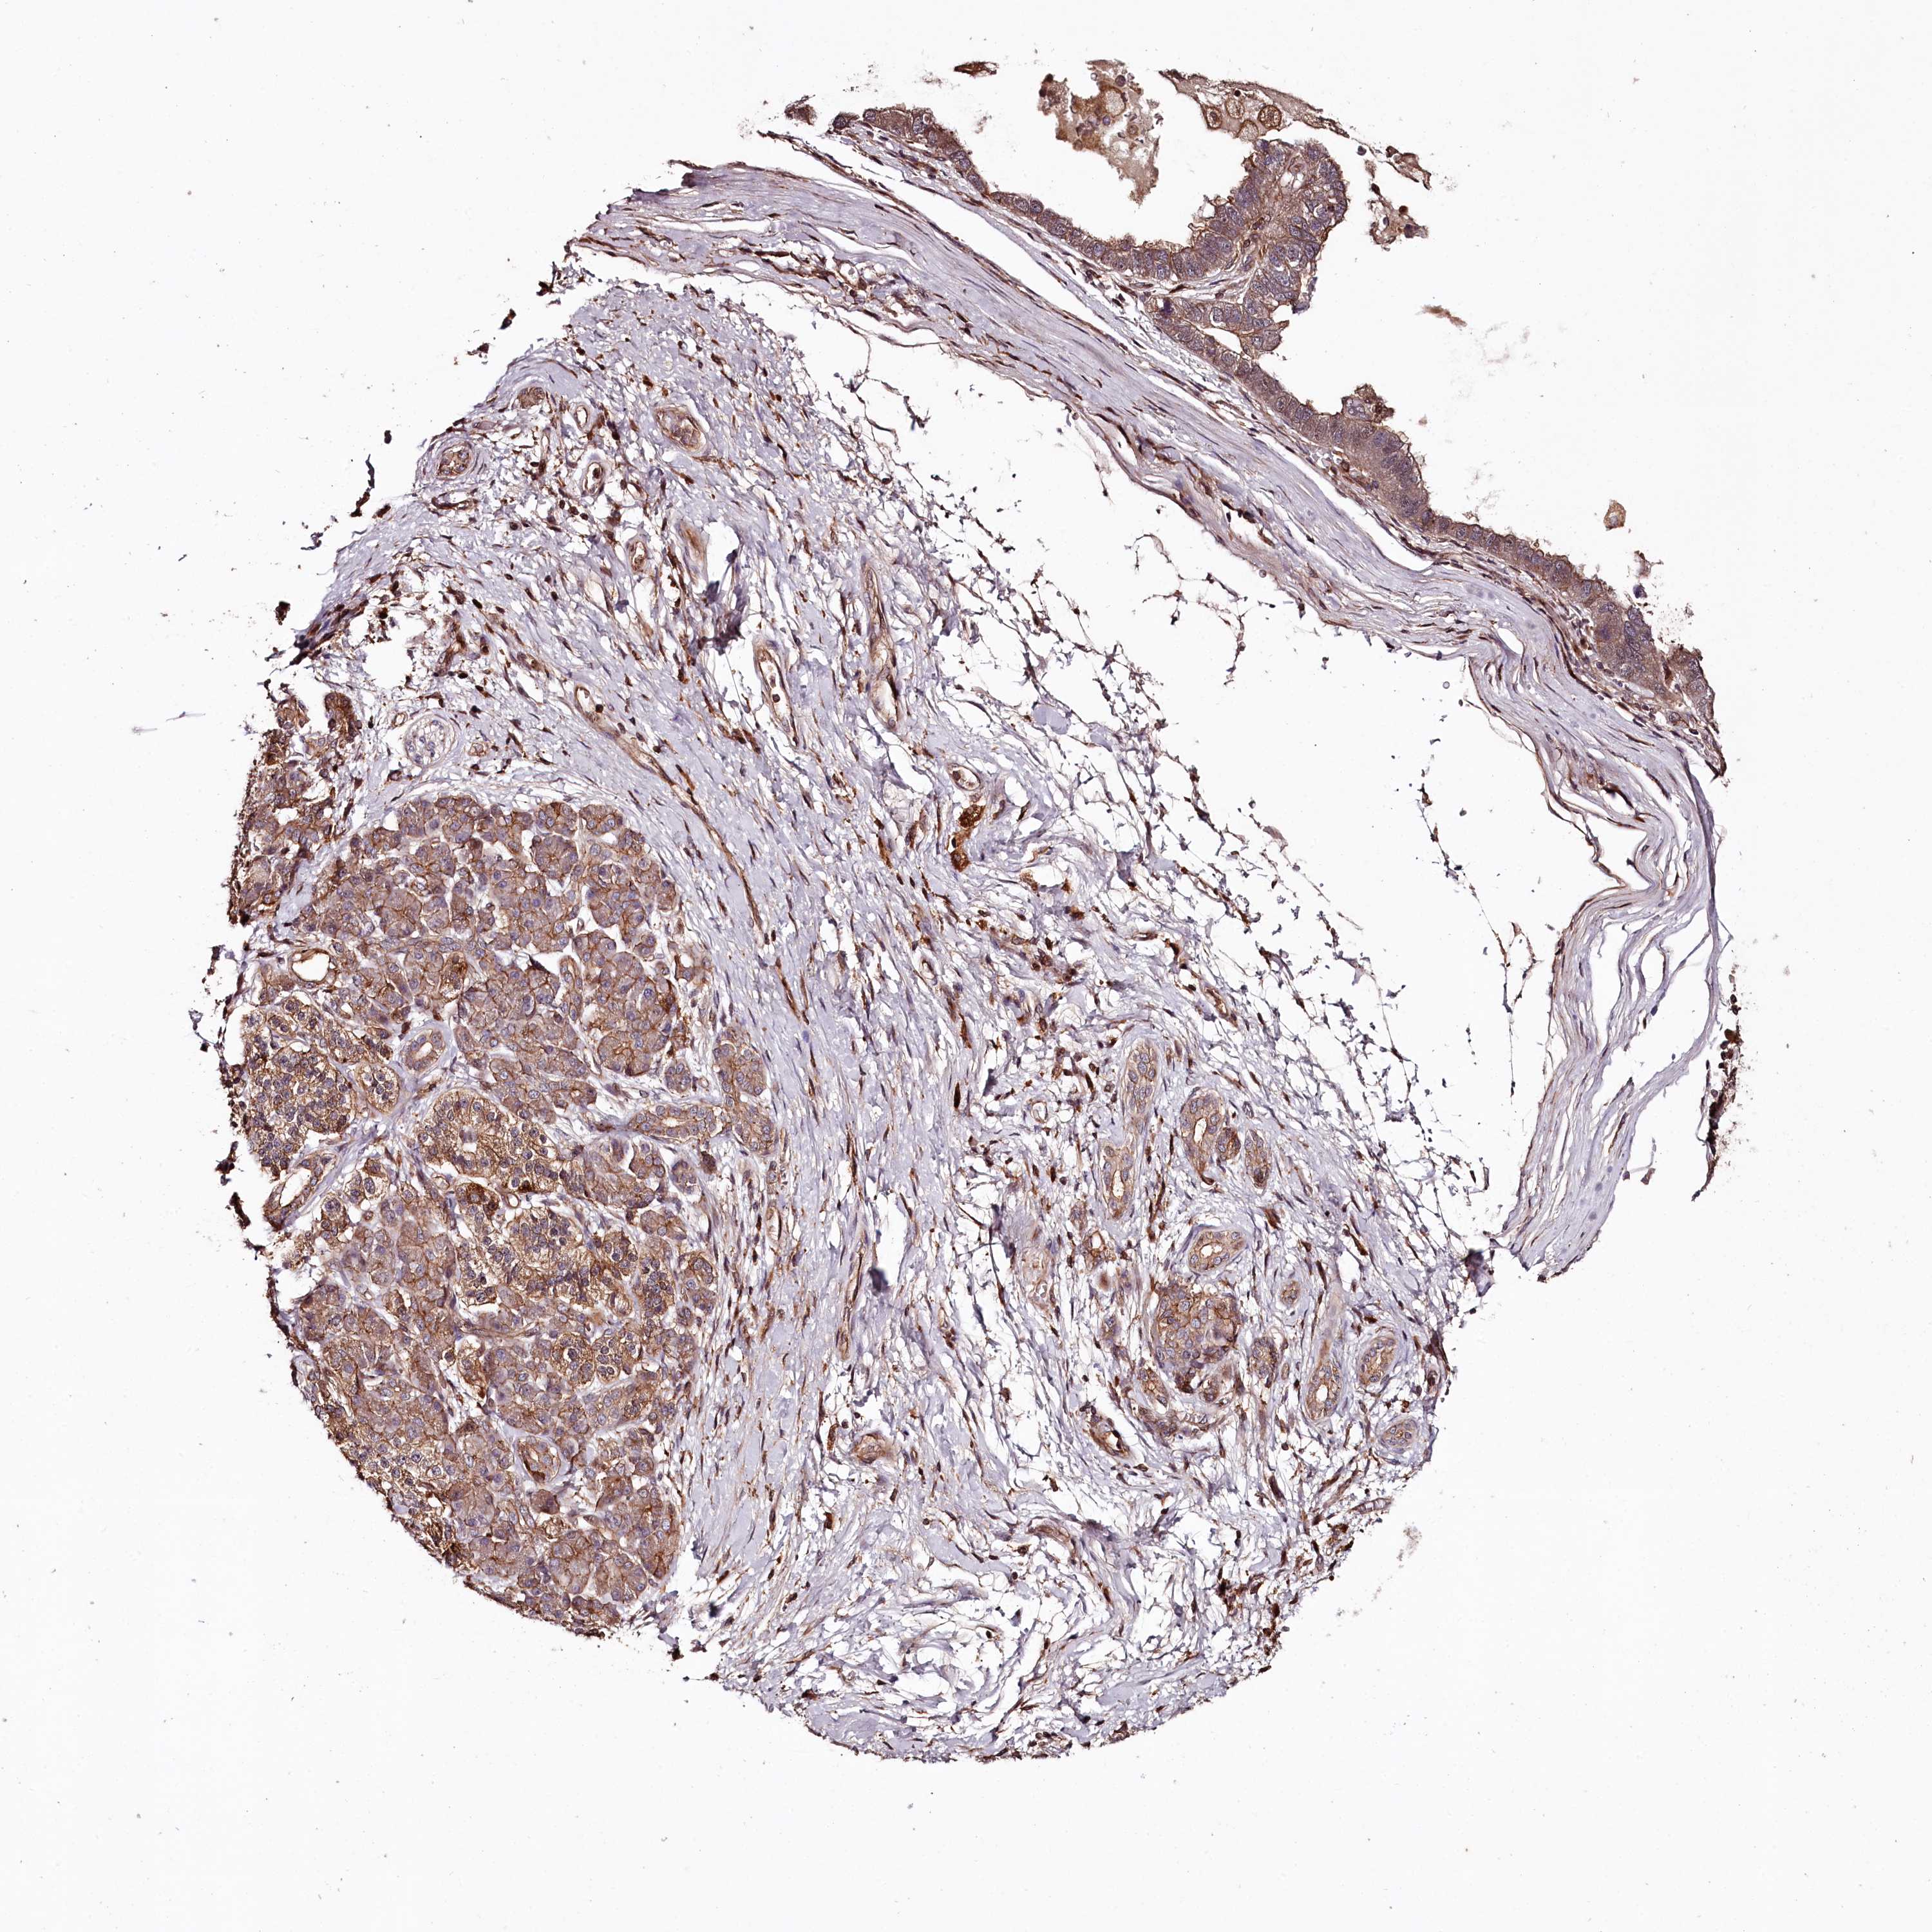

PANCREATIC CANCER - Protein expressioni

A mouse-over function shows sample information and annotation data. Click on an image to view it in a full screen mode. Samples can be filtered based on level of antibody staining by selecting one or several of the following categories: high, medium, low and not detected. The assay and annotation is described here.

Note that samples used for immunohistochemistry by the Human Protein Atlas do not correspond to samples in the TCGA dataset.

Antibody stainingi

Antibody staining in the annotated cell types in the current human tissue is reported as not detected, low, medium, or high, based on conventional immunohistochemistry profiling in selected tissues. This score is based on the combination of the staining intensity and fraction of stained cells.

Each image is clickable and will lead to virtual microscopy that enables deeper exploration of all samples and also displays staining intensity scores, fraction scores and subcellular localization as well as patient and tissue information for each sample.

Antibody HPA038061

Staining

High

Medium

Low

Not detected

Intensity

Strong

Moderate

Weak

Negative

Quantity

>75%

75%-25%

<25%

None

Location

Nuclear

Cytoplasmic/membranous

Cytoplasmic/membranous,nuclear

Adenocarcinoma, NOS